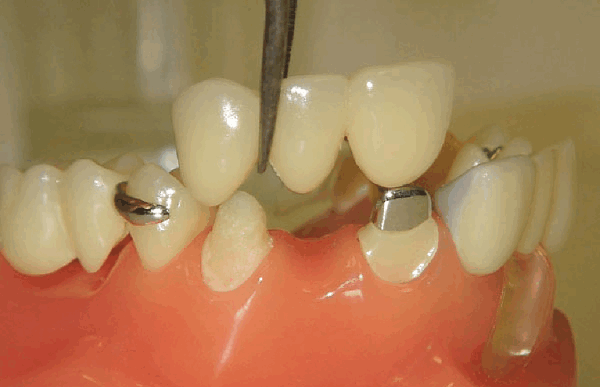

ПОДГОТОВКА ОПОРНЫХ ЗУБОВ

Конструкция для протезирования нуждается в опоре, поэтому необходима установка специальных коронок на опорные зубы, которые принимают на себя сложную жевательную нагрузку и тяжесть протеза. Для выполнения своих задач опорные зубы должны быть в прекрасном состоянии.

До установки конструкции специалист подготавливает опорные зубы, создавая плотный контакт между коронкой и зубом с целью обеспечения максимально физиологичного распределения нагрузки на зубы и предотвращения возможного развития кариозного поражения.